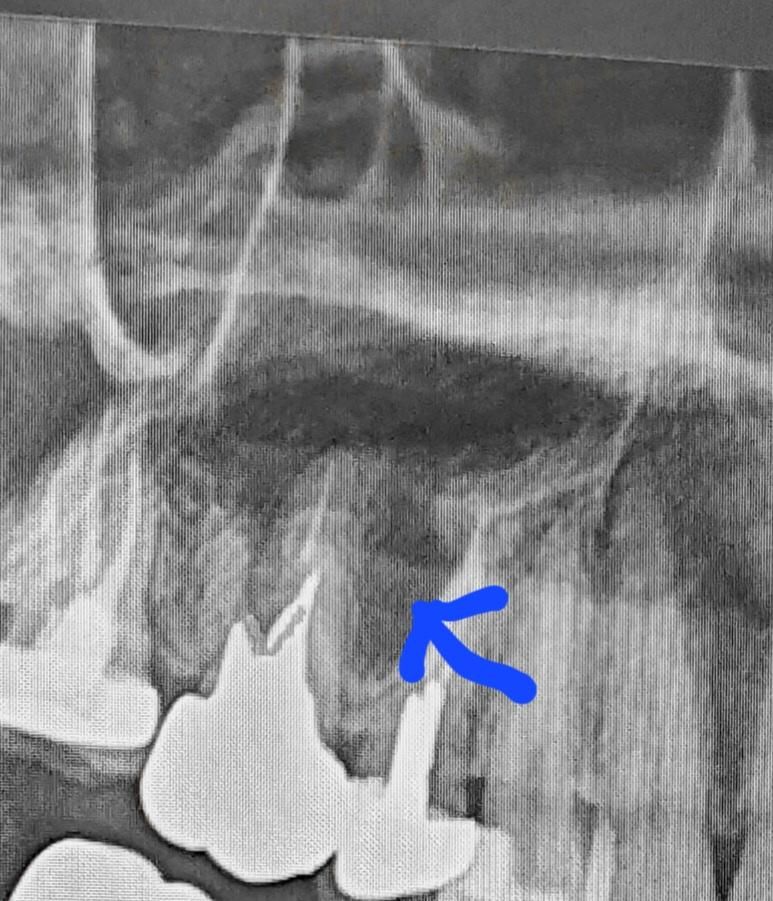

이거 뿌리쪽에 염증있는건가요? 치과에서는 좀지켜보자합니다

예전에 치료했던건데 최근근처잇몸이 부풀고 누르면아파서 찍었는데 확실하지않다고하시네요 저발치해야하나요? 시간이 많이없어서 치과가기힘든데 대학병원 가야하는건아니죠?

사진상으로는 염증이 있을 가능성이 높아보이며 발치의 가능성도 어느정도는 있어보입니다.

치아 주변으로 잇몸뼈가 약간 녹아 있는거 같습니다. 염증일 가능성이 높으니 일단 잇몸치료라도 받아보시는게 좋을것같습니다.

치아 주변의 뼈 밀도로 보았을 때 염증일 가능성이 큽니다. 또한 잇몸 통증이 나타났다면 이미 염증이 심해 잇몸을 뚫고 농이 나오고 있을 가능성이 큽니다. 정확한 위치를 위해 ct 등을 촬영해보아야 하며 염증이 너무 크다면 발치를 해야할 가능성도 높아 보입니다. 꼭 대학병원을 방문하지 않아도 되며 가까운 치과를 방문해보시길 바랍니다.

엑스레이상에서는 염증이 있는 상태로 보입니다. 신경치료를 했으나 염증이 온전히 사라지지 않는 경우도 있습니다. 만성 염증 상태에서는 잇몸 증상이 생겼다, 없어졌다 반복하기도 하고 별다른 증상이 없기도 합니다. 지금으로서는 큰 증상이 없다면 지켜보다가 증상이 생기면 빼거나, 재신경치료를 해봅니다.